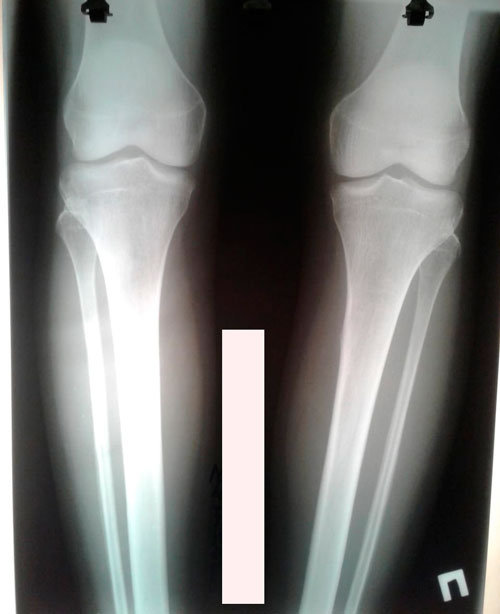

Дата снятия аппаратов - 02.07.2019г.

Срок сращения - 89 дней.